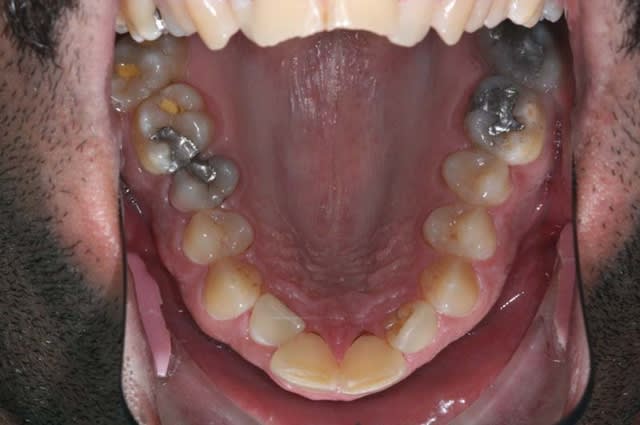

il ne peut plus croquer (mobilité des dents Sup.)

Il grince surtout sur les incisives centrales et latérales,

Pourtant les bruxomans ont généralement un parodonte qui s'adapté à cette pathologie, donc ce n'est pas ça qui devrait causer des mobilités...

C’est un fumeur? Il a une mobilité augmentée des incisives mais aucun signe d'inflammation. Peu de plaque et de tartre, peut être une parodontite agressive?

En tout cas il faudrait vérifier et corriger les restaurations existantes